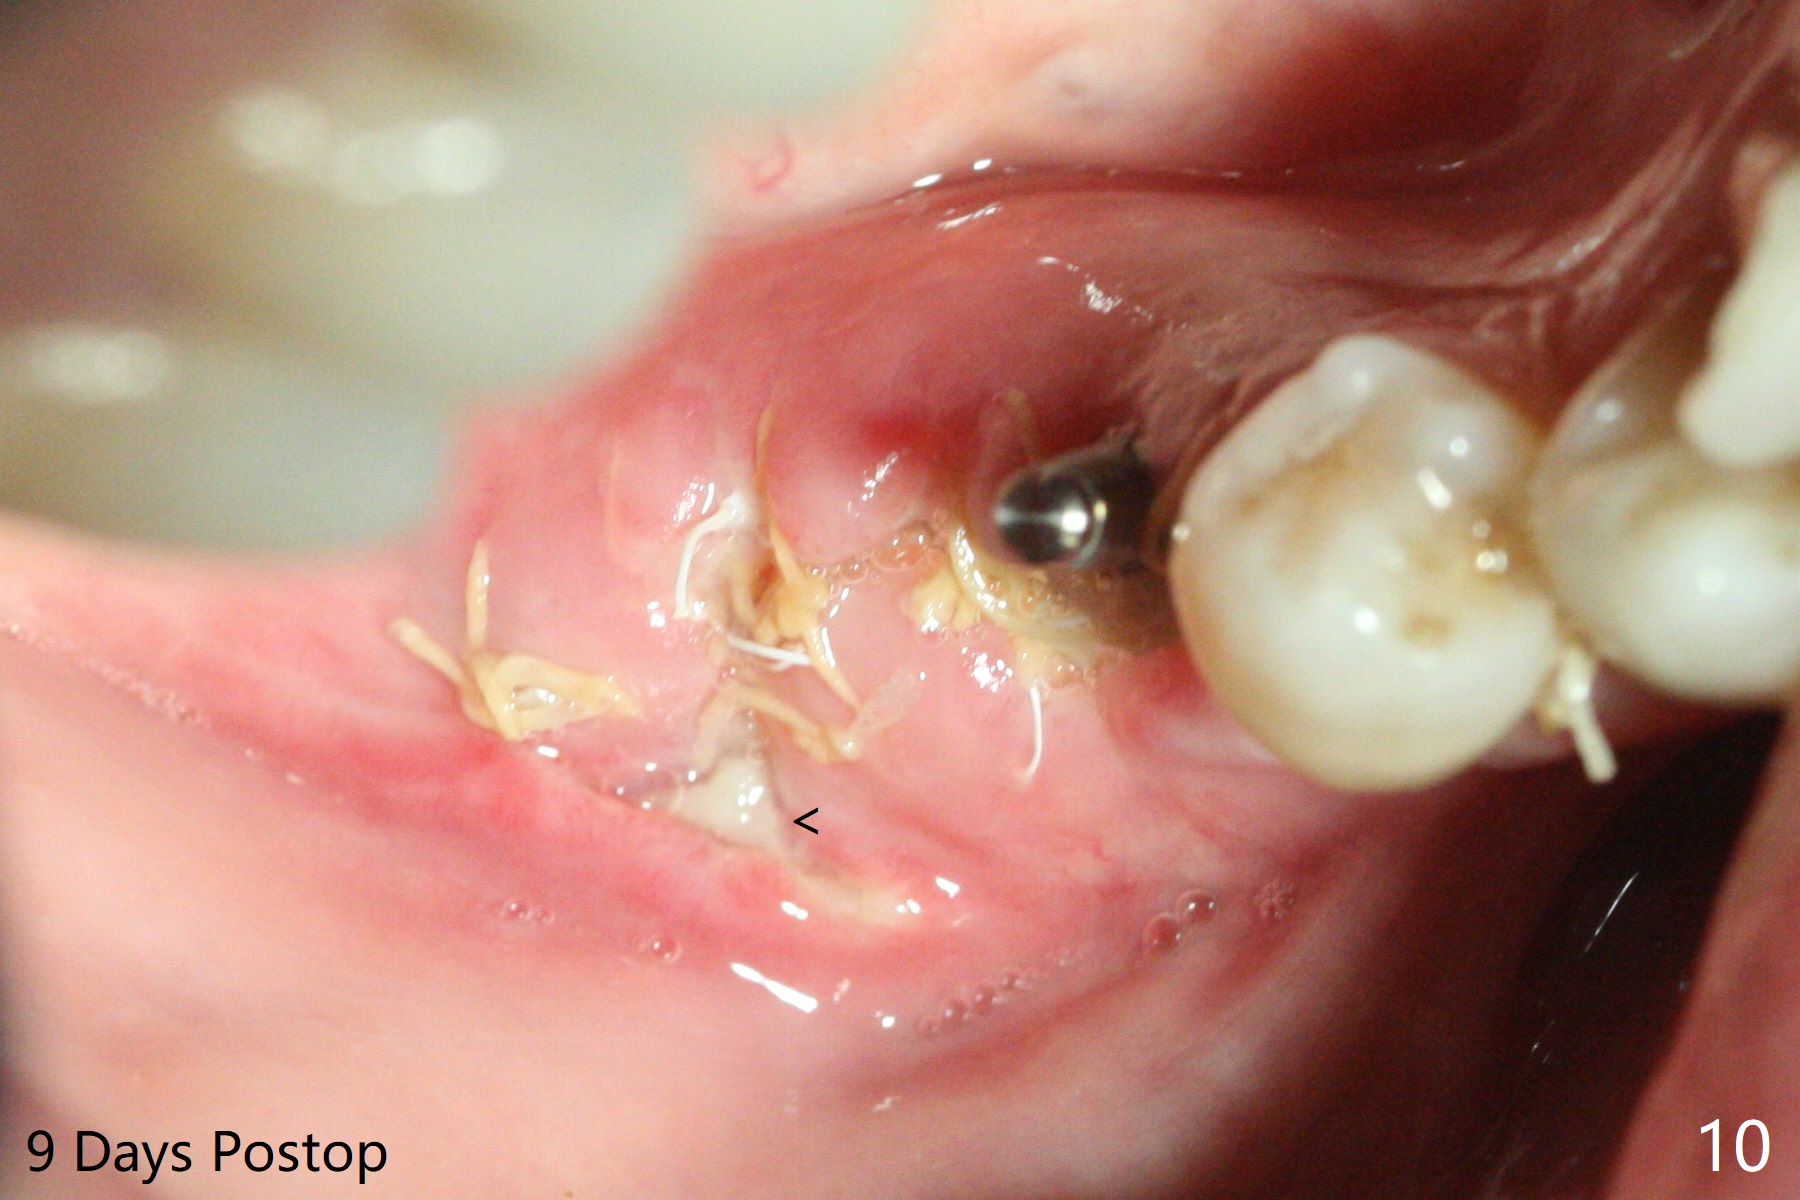

The implant at #30 was also buccally placed (Fig.6,7) and should be corrected in the same manner (Fig.7 green). Due to the bone being harder in the molar region, a smaller and shorter implant (4x11 mm vs. 5x13 mm) shifts slightly buccally while being placed (Fig.8,9). Since primary stability is lower (<20 Ncm vs. 35 Ncm associated with the implant #29), an abutment is not placed, which may be favorable to healing, but it is difficult to achieve primary closure. After bone graft (Fig.9 *) and 2 layers of PRF, Cytoplast is placed. Cytoplast appears to be exposed buccally (Fig.10 <) and occlusally (Fig.11 ^) asymptomatic 9 days postop. Exposure of Cytoplast is more distinct without sign of infection 15 days postop (Fig.12). The patient returns with chief complaint of "foul smell" 7 weeks postop (coronavirus lockdown). Although the Cytoplast exposes more (Fig.13 (* exposed; @ unexposed)), the underlying gingiva remains healthy (Fig.14). While the bone height decreases at #29, the bone density at #30 increases 4.5 months postop (Fig.15). The gingiva heals. The implant at #30 is uncovered 6 months postop. The lingual plate has to be removed for the uncover, while the coronal end of the buccal one is missing. No bone graft is added. When the 4.5x4 mm healing abutment is removed 6.5 months postop, the buccal plate looks concave at #30 (Fig.16' *). The buccal plate looks thin at #29 with a cotton roll placed buccally (Fig.16 R). The lingual plate at #29 is coronal to the buccal one (Fig.17). The buccal gingiva at #29 is quite long (Fig.18). The coronal buccal plate appears to be missing (Fig.19 >), which will be watched. A 4.5x7.5(4) mm cemented abutment is torqued (Fig.20).